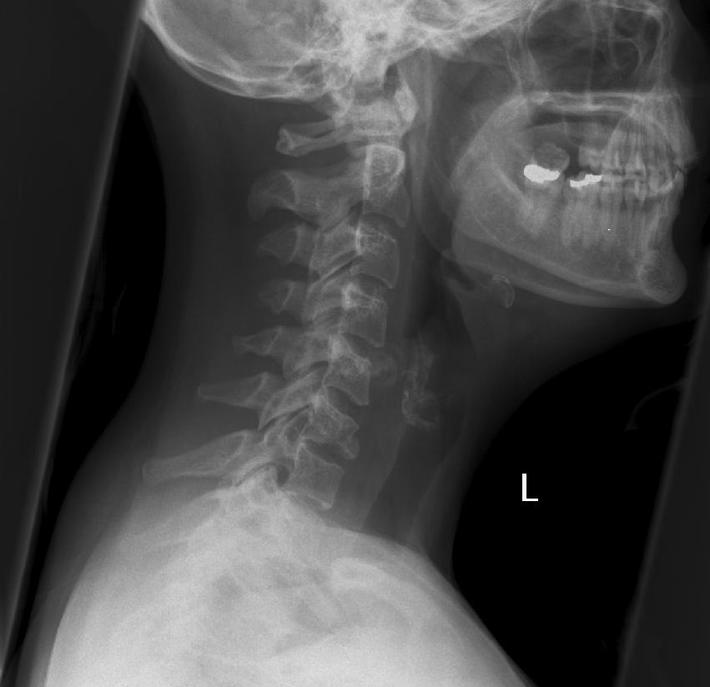

This lateral c-spine fracture shows a compression fracture of C6 with an anterior-inferior vertebral body fragment. There is widening of the interspinous distance (seen well on the AP view, click image to see). Note loss of vertebral body height on both AP and lateral views.

Also known as flexion/extension fracture, the findings are: compression fracture of a (usually lower) cervical vertebra, with anterior-inferior corner separation (the “teardrop”); widening of the interspinous distance at the same level or the level above; and widening or mild rotatory subluxation of facet joints. There may be slight associated listhesis. CT scan is indicated for further assessment of these fractures, as there are often other fractures not seen on plain film. Teardrop fractures are universally unstable, with disruption of anterior, middle and posterior columns. There is a high incidence of associated cord injury, which is best assessed with MRI, including a gradient-echo sequence for cord haematoma.